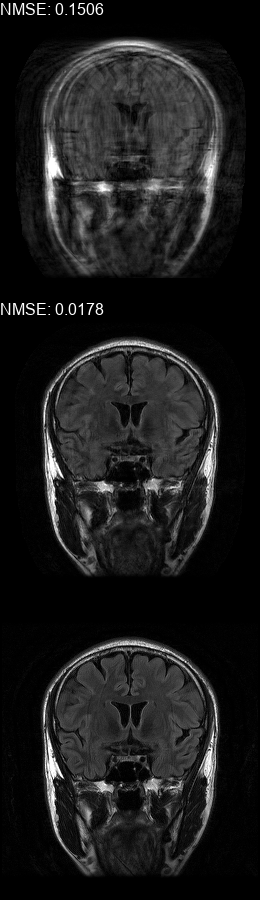

Results  Experimental results using the two presented datasets, for the fully-sampled and under-sampled k𝑘k-space scan orders, are shown in Table 1. The table presents the Normalized Mean Square Error (NMSE) obtained for each of the scan orders. For the Transaxial dataset, we only show the results for the challenging task where the DP contains only up to 707070 columns of k𝑘k-space data. All methods are able to reduce the NMSE of the corrupted scans, however the methods that incorporate the DC layer achieve a much better result. These results match our subjective visual impression of the motion-corrected images, as may be seen in Fig. 3 for simulated motion in a fully-sampled k𝑘k-space data, and Fig. 4 for an under-sampled k𝑘k-space data.

Figure 3: Motion corrected images from the Diverse dataset calculated using the 𝒮260subscript𝒮260\mathcal{FS}_{260} scan order presented in Fig. 1b. The bottom row shows the motion-free image. The top row shows the motion-corrupted images. The middle row shows the corrected images calculated using our method. (a) contains a motion at t1=87subscript𝑡187t_{1}=87, (b) contains two motions at t1=46subscript𝑡146t_{1}\!=\!46, t2=170subscript𝑡2170t_{2}\!=\!170, (c) contains three motions at t1=72subscript𝑡172t_{1}\!=\!72, t2=227subscript𝑡2227t_{2}\!=\!227, t3=248subscript𝑡3248t_{3}\!=\!248, (d) contains two motions at t1=112subscript𝑡1112t_{1}\!=\!112, t2=216subscript𝑡2216t_{2}\!=\!216, (e) contains a motion at t1=66subscript𝑡166t_{1}\!=\!66, (f) contains three motions at t1=65subscript𝑡165t_{1}=65, t2=135subscript𝑡2135t_{2}\!=\!135, t3=159subscript𝑡3159t_{3}\!=\!159.